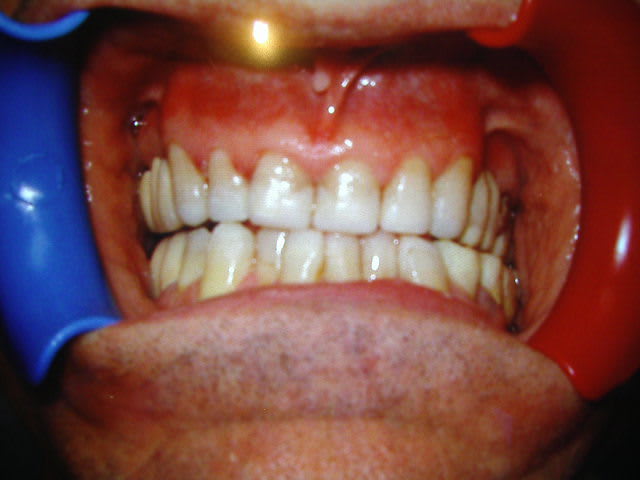

Lui (photos d'avant)c'est un cas terminé, bridges/coiffes post et compo ant, a porté gouttiere 6mois avant.

La photo "terminée" est celle d'une lateralité et donc effectivement il est de travers mais c'est voulu.....

D'autre part, elle a été prise au bout d'une séance de plus de 5 heures: pose coiffes et bridges CCM post à droite et pose de barrettes compo sur bridges préexistants à gauche (on voit la démarcation) + réalisation de compo directs de 13 à 23 et de 44 à 33.... depuis j'ai repris les fonctions en lateralité et en propulsion de façon à mieux equilibrer tout ça....

Donc le cas présenté est partiel mais j'ai pas voulu surcharger le site d'iconographie et j'ai pas refait de photos depuis...